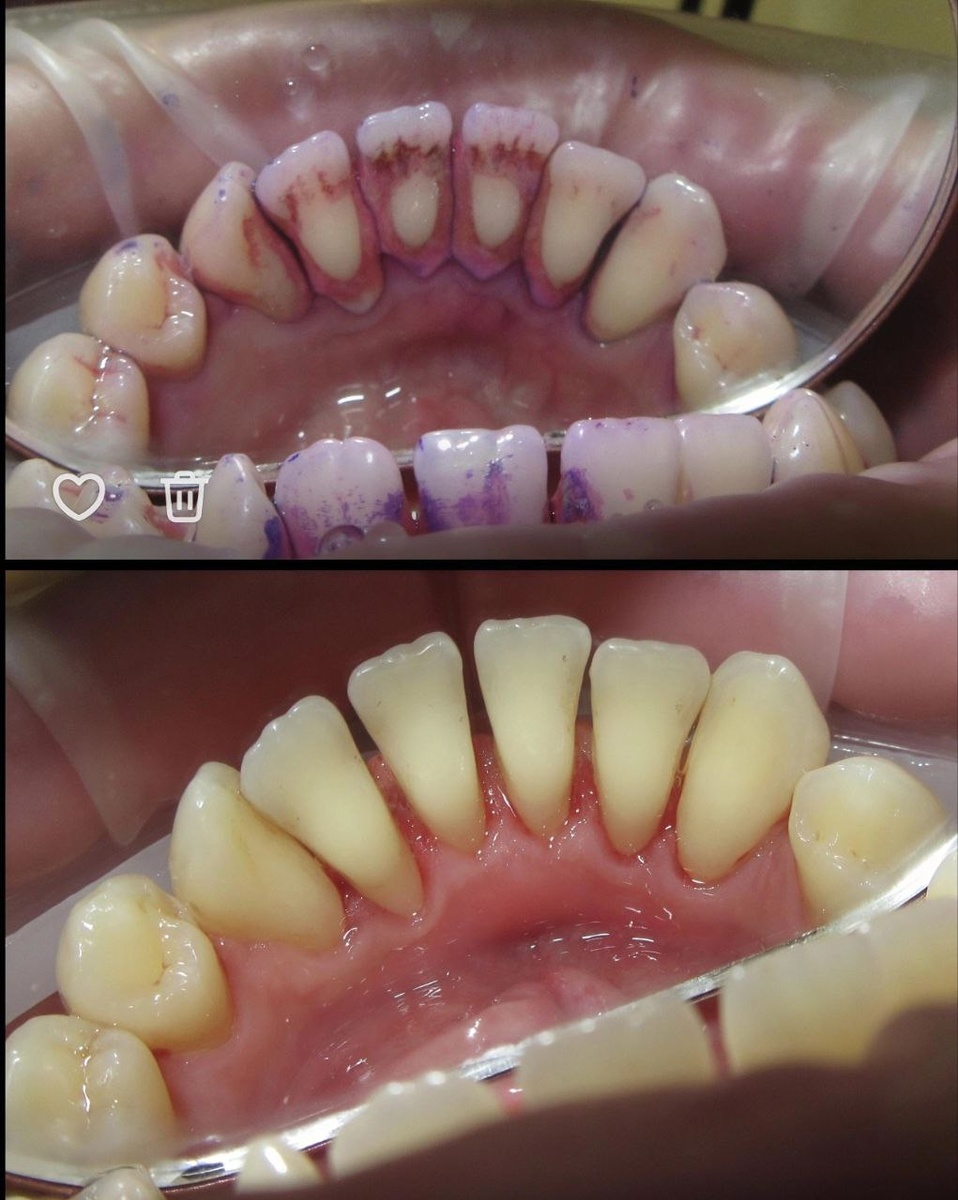

📌Каждый день — и вы реально спасаете свои дёсны.

Убираем налёт → снижает воспаление → меньше кровоточивости → свежее дыхание → меньше шансов заработать кариес между зубами.